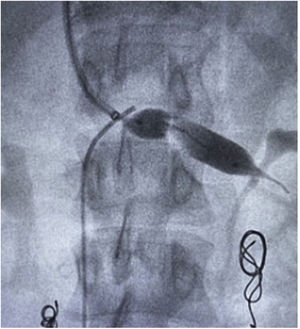

Surgical techniqueThe principles applied were urgent LRV pressure control, treatment of the hematuria, venous drainage derivation and congestive pelvic syndrome origin resolution. All the patients remain 24h postoperative in hospital observation. The repair was performed via endovascular access, after local anesthesia and sedation. The right common femoral and the left internal jugular vein was punctured with ultrasound guide and a 6F introducers sheath were inserted. The LRV was catheterized with a Cobra 2 5F diagnostic catheter and phlebography was performed. This confirmed critical stenosis of the LRV and the pelvic varicose veins on the left, with a dilated left gonadal vein (Fig. 1). The stenosis pressure gradient was measured in all patients. Through the internal jugular access, balloon LRV angioplasty was performed (Fig. 2) and then deployment of a e-Luminex self-expanding nitinol bare metal arterial stent (10–12mm×40mm) (Figs. 3 and 4) was performed resolving the NCS (Fig. 5). Additionally, identified pelvic varicose veins were embolized using Concerto coils (20mm×50mm) through the basilic vein using a multi-purpose catheter. No dietary restrictions were imposed, and oral food intake was initiated in the first 3 postoperative hours. No need for a postoperative ICU. Postoperative anticoagulation for 6 months using rivaroxaban and then switching to salicylic acid for another 6 months was prescribed to all patients. The postoperative patients follow-up was performed using Doppler ultrasound in the 6 months and physical examination in all face-to-face clinical outpatient consults.

During the period from January 2019 to April 2022, 553 patients were treated for congestive pelvic syndrome. Only 11 patients have clinical (hematuria, varicose pelvic veins, and left flank pain), imaging diagnostic criteria (abdominal veins Doppler ultrasound or abdominal CT with a SMA – abdominal aorta angle less than 39°) and an average of LRV–IVC pressure measurement comparison difference of 6mmHg for NCS. The 100% were female patients. All the patients were under 65 years old and underwent endovascular approach with LRV balloon and arterial stent angioplasty. The 100% of patients had collateral venous flow restored in the final control phlebo-cavography. The average age was 46.5 years old. Ten of the patients had an anterior type of NCS and only 1 had a posterior type of NCS (Fig. 6). None of the patients had NCS due to secondary causes such as pancreatic head tumors.